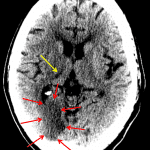

- Hypodensity with loss of gray-white differentiation in the right PCA territory, including the right occipital lobe and ventrolateral right thalamus

- Right PCA territory infarct

Hypodensity and loss of gray-white differentiation in the right occipital lobe concerning for acute/early subacute ischemia. Hypodensity in the ventrolateral right thalamus represents age-indeterminate ischemia. Both of these areas are in the right PCA territory. MRI could further assess the extent of ischemia.

No mass effect or evidence of hemorrhagic transformation.